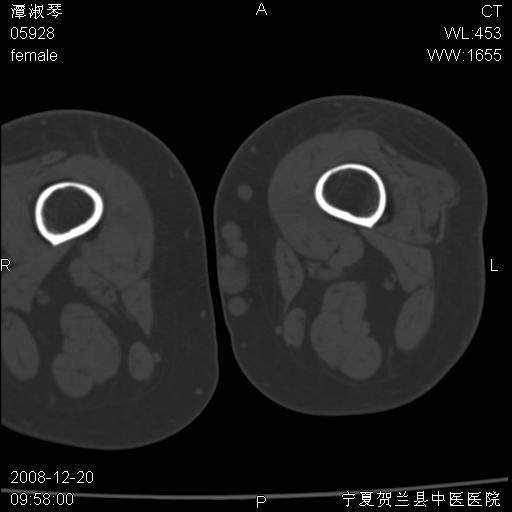

标题: CT17526:请各位看看是啥? [打印本页]

标题: CT17526:请各位看看是啥?

支持骨梗死,退行性骨关节病,膝关节积液.

左股骨下段骨梗死。双膝退变。

左胫骨下端松质骨及髓腔内可见点片状高密度灶,骨皮质无明显膨胀及变薄。病变范围较长。支持骨梗死,退行性骨关节病,膝关节积液